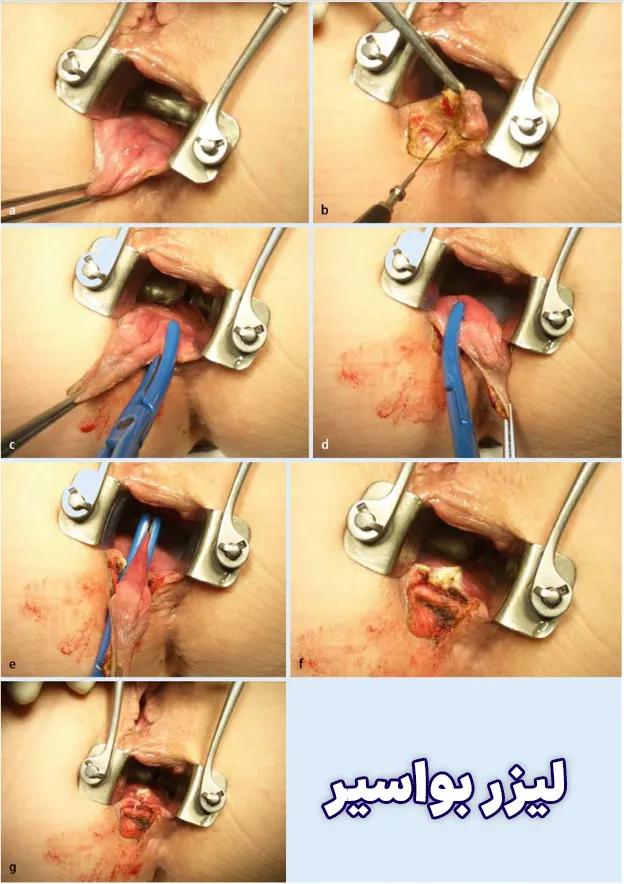

- درمان با جراحی و لیزر

بله هموروئید یک بیماری شایع است و به روش های مختلفی درمان می شود. در بین روش های موجود لیزر هموروئید ایمن تر بوده و درصد موفقیت بالایی دارد.

درمانهای جراحی برای هموروئید کدامند؟

- هموروئیدکتومی سنتی و لیزر: بافت اضافی که باعث خونریزی می شود با جراحی برداشته می شود.